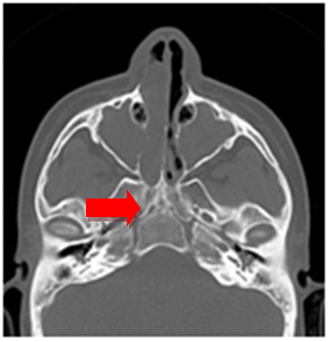

PCD is a rare, autosomal recessive disease with altered ciliary motility resulting in chronic upper and lower airway disease.3 Because of its low prevalence, there are few studies with significant numbers of cases, which makes it difficult to perform protocols and follow-up guidelines in these patients. A prevalence of 68% of nasal polyposis (Figure 1) is reported in these patients, 93% of rhinitis and 100% of signs of chronic rhinosinusitis (Figure 2).3 Functional endoscopic sinus surgery (FESS) is frequently indicated in cases of failure of medical treatment. It may be useful to decrease or eliminate upper and lower airway infections in these patients.4

Figure 2 CT scan. Pansinusitis.

Almost all patients with PCD have a diagnosis of severe pansinusitis on Computed Tomography scan.6 Frontal and/or sphenoidal sinuses are hypoplastic or aplastic on 73% of the affected parienta. Therefore it is important to the diagnostic suspicion of PCD having a tomographic finding of aplasia or hypoplasia in the frontal and sphenoid sinuses (Figure 3).7